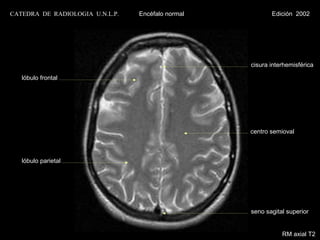

CATEDRA DE RADIOLOGIA U.N.L.P.   Encéfalo normal            Edición 2002

cisura interhemisférica

lóbulo frontal

centro semioval

lóbulo parietal

seno sagital superior

RM axial T1 con contraste